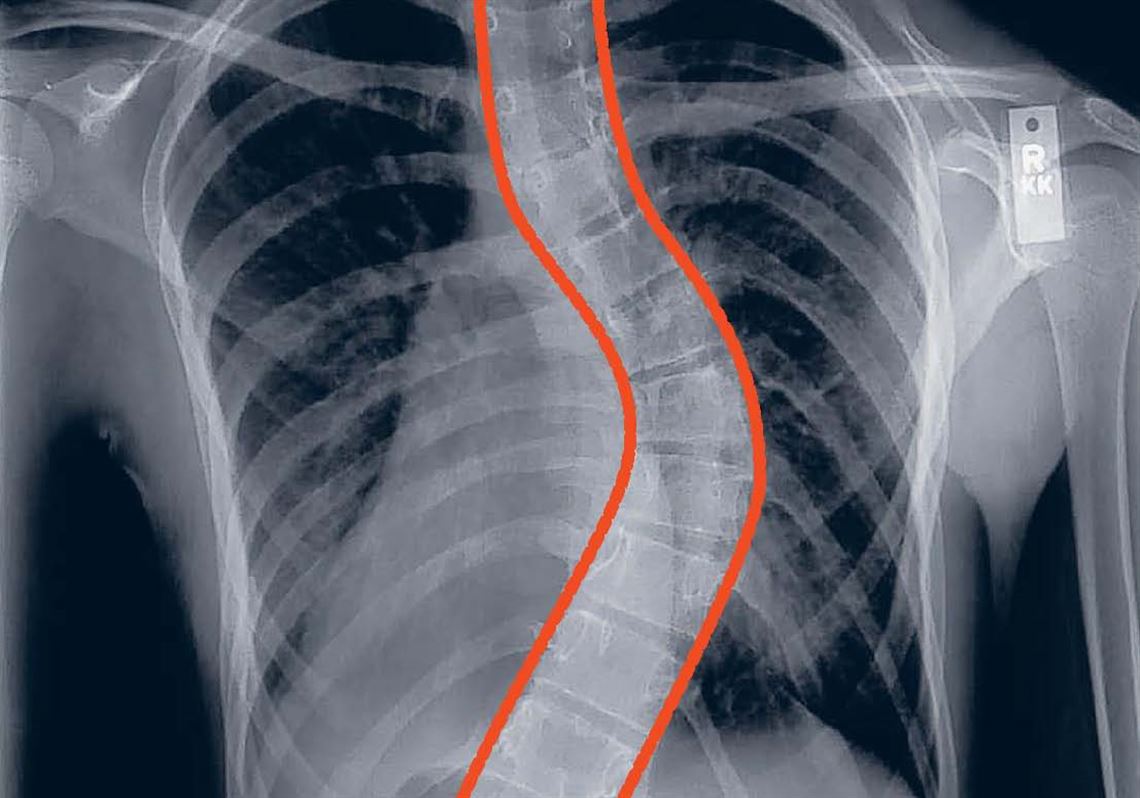

ALIF-Spine surgery Approaches | Dr. Efe's Medical Art Store, Ahead of the curve: Surgery for scoliosis no longer so「脊椎脊髄の手術 = Illustrated Surgery of Spine & Spinal Cord 第2巻」戸山 芳昭 / 花北 順哉定価: ¥ 240002015年初版状態:カバーに少スレ、小口にヨゴレ、角にヨレありますが、通読に支障はありません。※画像で状態をご確認ください。※古本につき、過度に状態を気にされる方はご遠慮ください。#戸山芳昭 #戸山_芳昭 #花北順哉 #花北_順哉 #本 #自然/医療・薬学・健康

Ahead of the curve: Surgery for scoliosis no longer so「脊椎脊髄の手術 = Illustrated Surgery of Spine & Spinal Cord 第2巻」戸山 芳昭 / 花北 順哉定価: ¥ 240002015年初版状態:カバーに少スレ、小口にヨゴレ、角にヨレありますが、通読に支障はありません。※画像で状態をご確認ください。※古本につき、過度に状態を気にされる方はご遠慮ください。#戸山芳昭 #戸山_芳昭 #花北順哉 #花北_順哉 #本 #自然/医療・薬学・健康